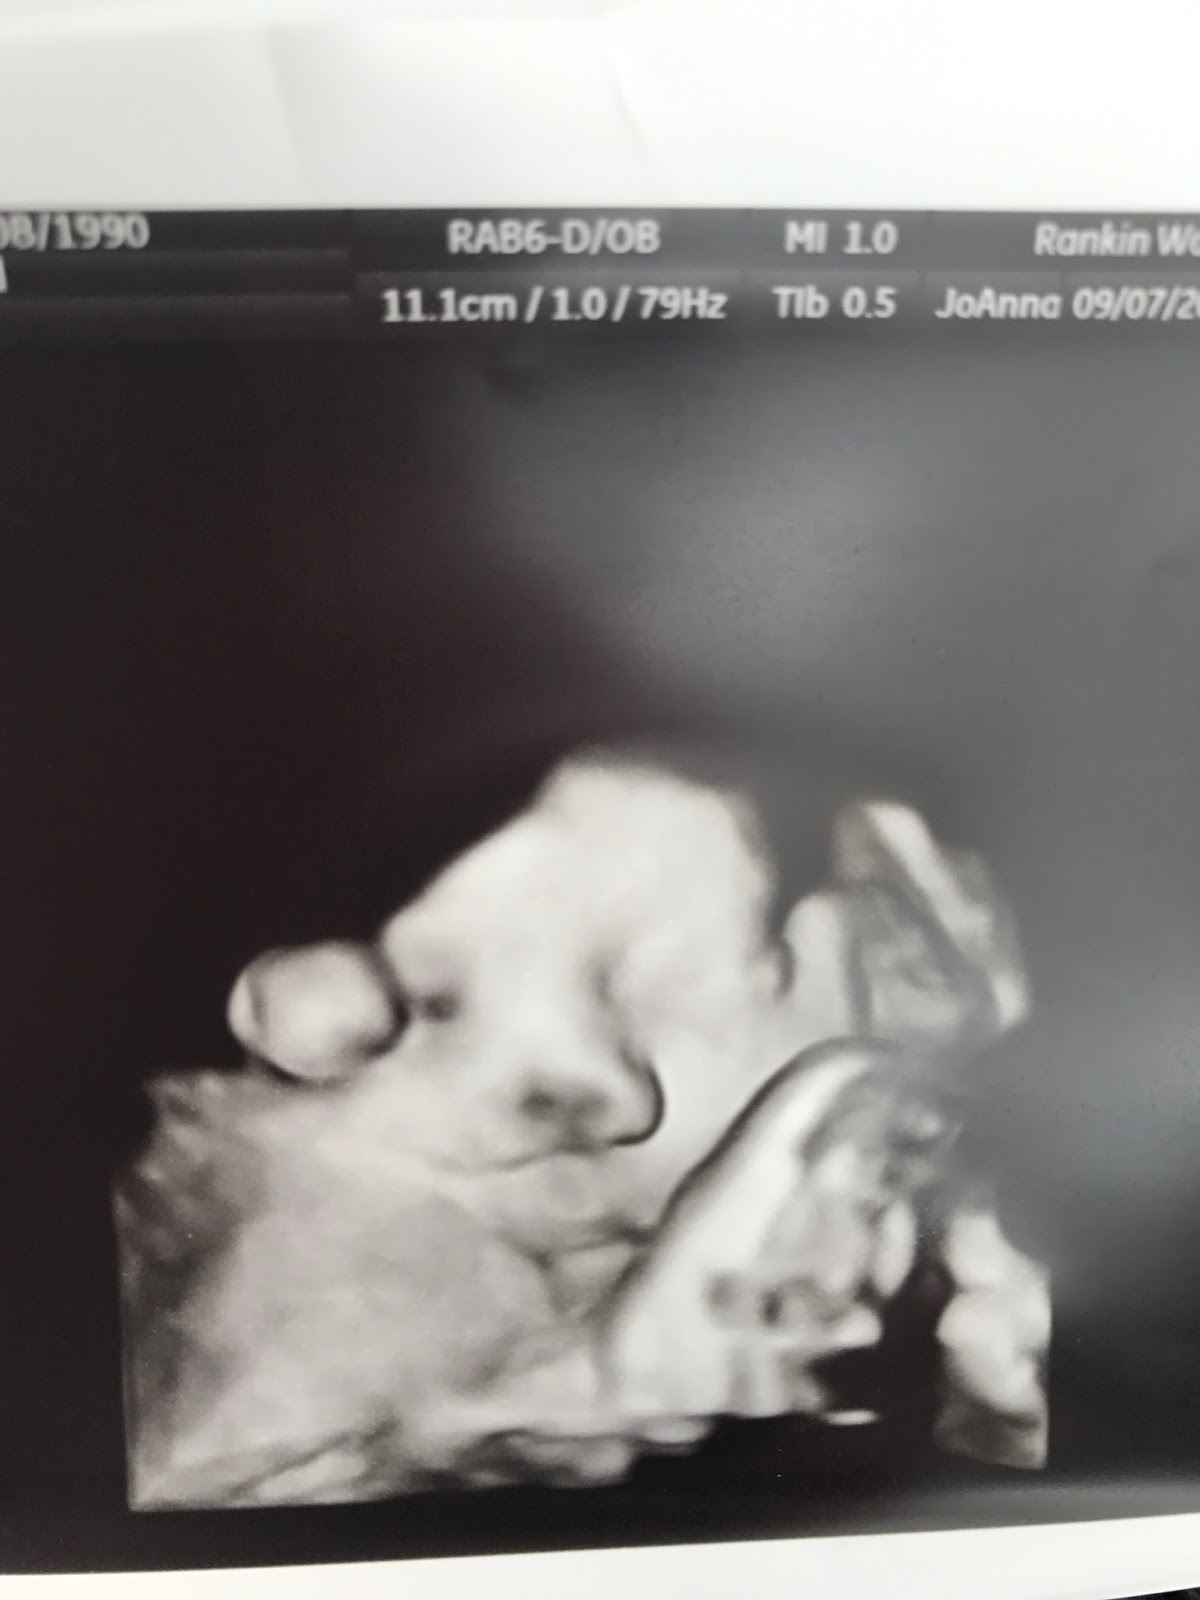

^36 week growth ultrasound--estimated her about 5 1/2 pounds--not the best pics but already knew she had Andrew's lips when I saw this pic and was so excited!!